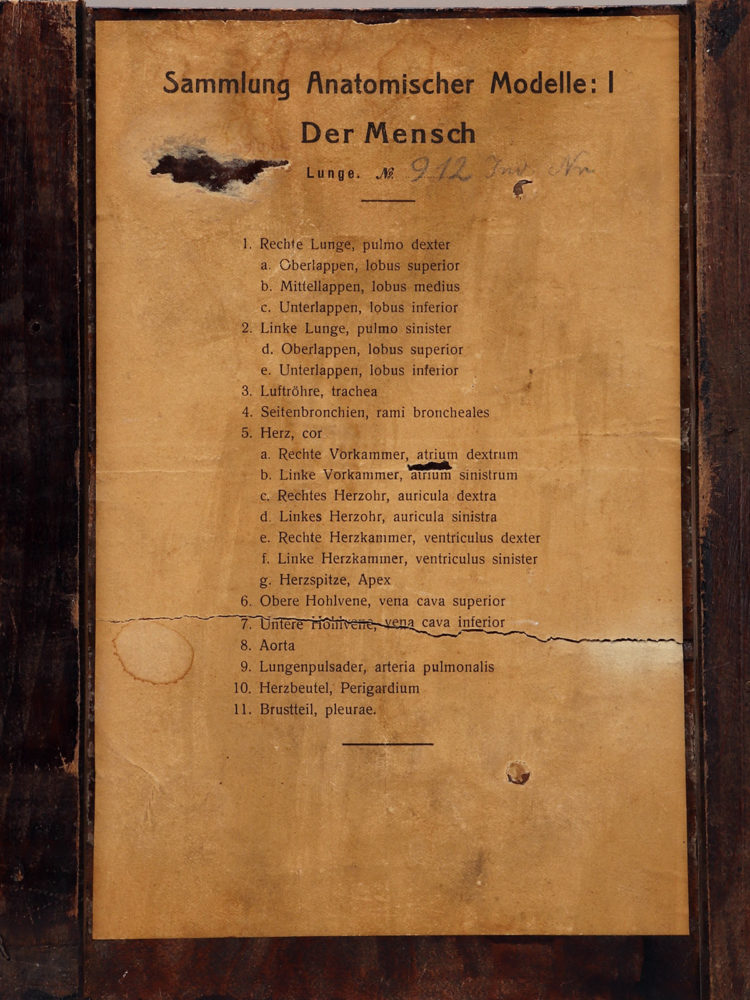

Rare anatomical model for class, depicting human lungs and heart, made out of painted plaster, mounted on a black fruit wooden base. By Louis M. Meusel, Germany circa 1920.